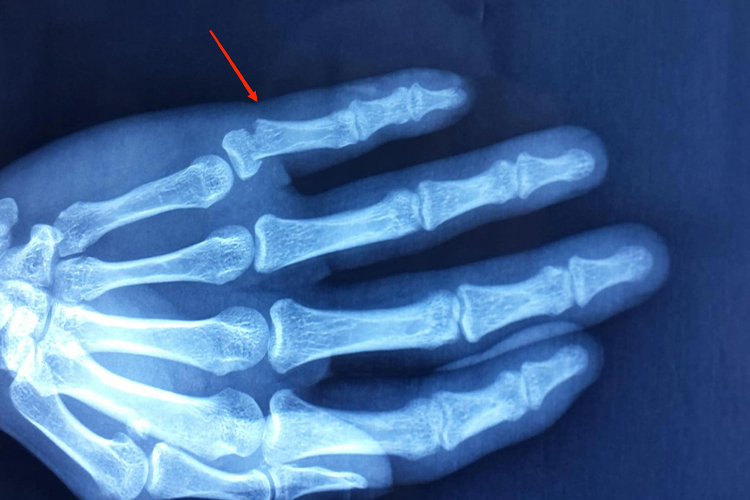

手指头骨折应为指骨骨折,受伤后可有局部肿胀、疼痛、压痛、畸形、异常活动,以及骨擦音、骨擦感、纵向叩击痛等表现。由于骨间肌、蚓状肌、屈指肌、伸指肌的牵拉,中节指骨基部骨折,骨折端向背侧成角,而近节指骨及中节指骨浅屈肌附着点以远的骨折,骨折端向掌侧成角,指骨基底部撕脱骨折,手指末节下垂呈锤状,多经影像学检查发现。

闭合性、稳定性指骨骨折原则上应该采用手法复位,并使用石膏托或铝板功能位固定。开放性的指骨骨折,无论创口情况和损伤的严重程度如何,均应立即复位,恢复患指血供,保护重要的血管神经,尽早修复撕裂的关节囊、韧带。常用的手部骨折固定方式有克氏针、微型钢板螺钉、微型外固定支架等。